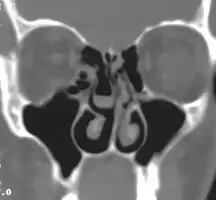

- Large concha bullosa

- Bilateral concha bullosa, larger on the left